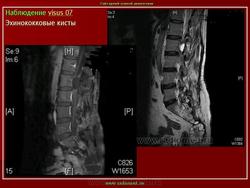

Магнитно - резонанснуютомография применяли на завершающем этапе неинвазивного диагностического обследования 13 больным эхинококкозом печени с целью детализации характера патоморфологических изменений в очаге поражения и уточнения степени вовлечения в процесс крупных сосудисто-секреторных структур.

Свободный выбор плоскостей изображения позволил уточнить топический диагноз. С другой стороны, благодаря высокому мягкотканному контрасту при МРТ выявили значимые дополнительные признаки паразитарных кист. Так, например, МРТ была наиболее информативной в выявлении неровностей внутреннего края кисты и начинающегося расслоения паразитарных мембран.

Несомненным преимуществом метода явилась возможность дифференцирования изменений в архитектонике печени с высокой разрешающей способностью. Вокруг гидатидных кист на МР -томограммах визуализировался ободок слабого изменения МР-сигнала (гипоинтенсивный на Т1 ВИ, гиперинтенсивный на Т2 ВИ) с нечеткими контурами, соответствующий перикистозным изменениям (рис 5а,б ). С помощью МР-волюметрии рассчитывали объем эхинококковых кист, объем непораженной паренхимы печени и степень выраженности компенсаторной гипертрофии органа. МРТ позволила диагностировать эхинококковые кисты в брюшной полости при сочетанном эхинококкозе без дополнительного контрастирования кишечника. При проведении МРТ были выявлены